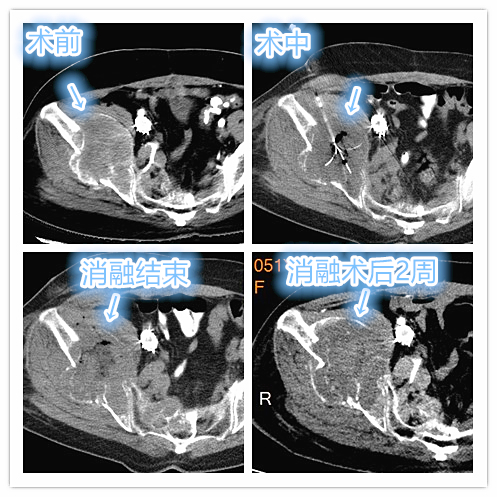

经介入栓塞后局部肿瘤已出现缺血、坏死,后期通过局部多部位、大范围射频消融,快速毁损肿瘤病灶,术后疼痛、肿胀感明显缓解。

骨转移瘤局部射频消融治疗